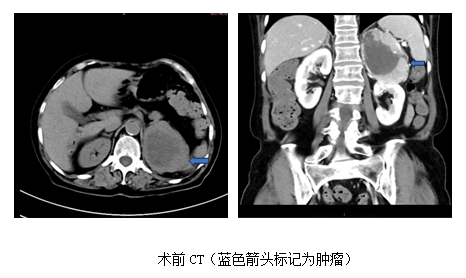

心内科后,赵永勇医师高度重视,予以高血压病因筛查,CT发现左肾上腺区8cm占位,考虑嗜铬细胞瘤可能,肿瘤密度不均匀,显著不均匀强化。同时,查24小时尿儿茶酚胺,显示多巴胺,去甲肾上腺素,甲氧基去甲肾上腺素3甲氧酪胺及香草扁桃酸升高数倍,目前西北区域仅欧美视频

开展的131I-MIBG检查显示左侧肾上腺区域明显阳性病灶,